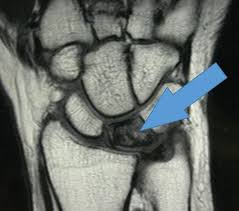

- Магнитно-резонансная томография (МРТ). Это «золотой стандарт» в диагностике дискоидного мениска и его повреждений. МРТ позволяет детально визуализировать все мягкие ткани сустава, включая хрящи, связки и мениски. Исследование дает точную информацию о форме, целостности и положении ДМ, что крайне важно для выбора тактики лечения.